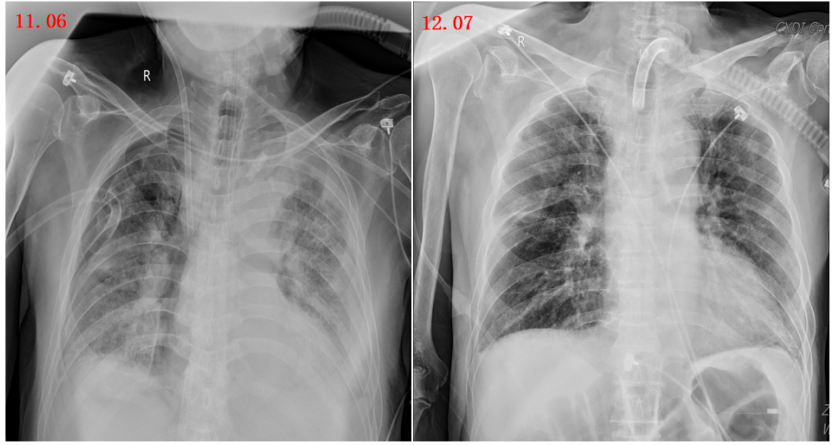

影像变化趋势

图7所示为患者ECMO(10月10日-11月10日)治疗期间影像学检查结果。患者氧合状况明显改善,肺部阴影有所吸收,但仍可见部分渗出影。鉴于影像学改变往往具有一定滞后性,因此拟行脱机试验。

图片

图7  患者影像学变化情况

由于患者住院时间较长,肌肉萎缩,呼吸肌力丧失,于1月15日行气管切开,镇静镇痛逐步减量,降低呼吸支持力度,同时采取措施促进胃肠功能恢复,并积极进行康复锻炼。12月7日复查胸片,可见肺部阴影进一步吸收(图9)

图9  复查胸片(2023-12-07)